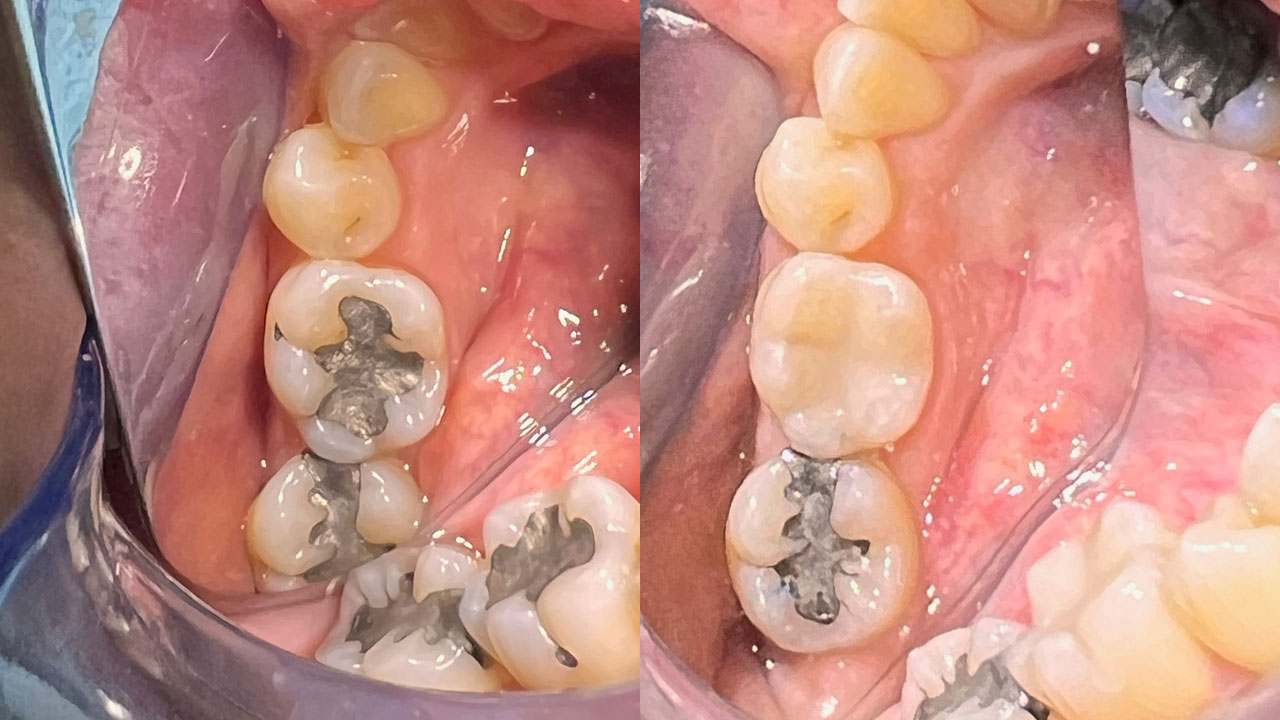

We’d like to let our results do the talking. Check out some of our amazing transformations in our Smile Gallery, combining a mixture of tooth coloured restorations, implant treatments, crowns, veneers, tooth whitening and full mouth rehabilitation.